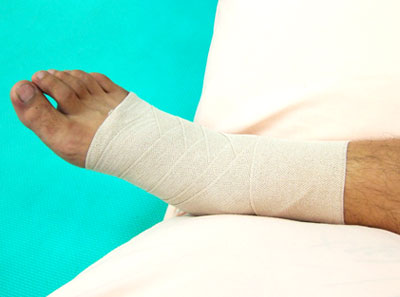

踝扭傷

踝關(guān)節(jié)扭傷后,不要繼續(xù)行走,也不要揉搓、轉(zhuǎn)動(dòng)受傷關(guān)節(jié),以免進(jìn)一步加重?fù)p傷。應(yīng)立即用冷毛巾或冰塊敷患處,有利消腫、止痛、緩解肌肉痙攣。24小時(shí)后方可改為熱敷。如果懷疑有內(nèi)出血,最好用彈性繃帶加壓包扎,但不要過緊,以免妨礙包扎部位以下的血液循環(huán)。如果懷疑有骨折,最好用夾板或就近找木棍固定受傷的踝關(guān)節(jié),并盡快去醫(yī)院就診。